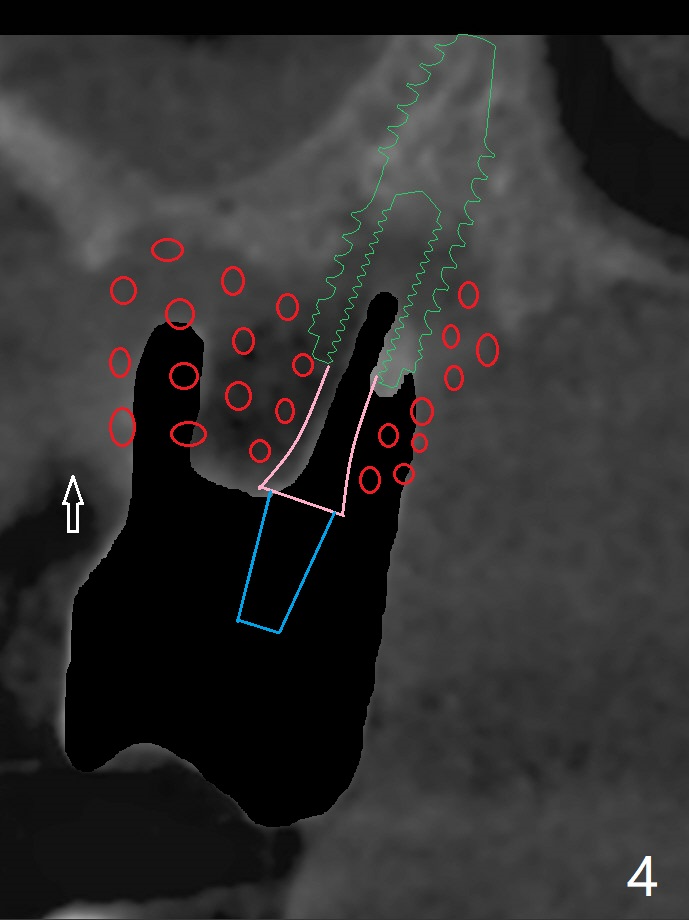

59岁女两年前就诊,主诉右上7,8之间食物坎塞,没有注意7骨质吸收(图一),以为是8过度延申所致拔除,而且远中颊侧,腭侧根断裂(间接说明咬合力大),前者拔除,而后者滞留。如果不拔除,现在支撑导板多好。两年后病人认为断根长出来,其实腭侧根尖仍在骨中(图二(半年前拍摄):箭头),而7骨质吸收更严重,松动2度,怀疑根裂(咬合力大)。同时病人可能有骨质疏松,拔除即刻种植,基台一定要短,一旦牙槽窝愈合,考虑取出临时牙冠,减少微动。取模前,进行渐进性负荷。术前服用Z Pack,准备上颌窦提升,PRFx2。CT显示上颌窦提升不需要,植体可以植入腭侧窝(图三)。 CT冠状切面(图四),矢状切面(图五)显示必须使用长袖的基台(粉红色)固定粘性骨粉(红色),这样植体(绿色)稍微可以种得浅些。箭头:cotton roll(颊侧牙龈沟)。为了让病人在制作导板时舒服些,利用邻牙做冠外固定7松动牙(III)。7颊侧软组织缺失(图六:*)。